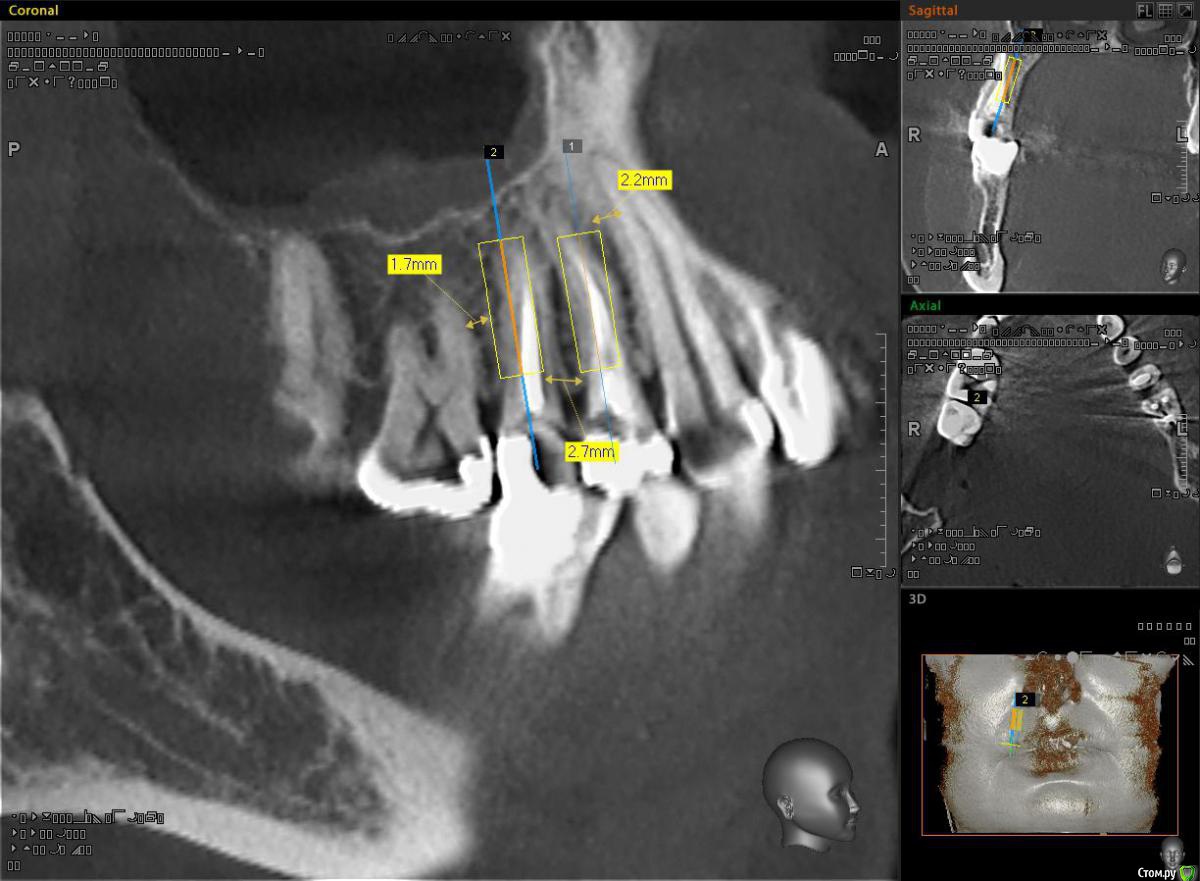

alekszander Опубликовано 3 ноября, 2015 Поделиться Опубликовано 3 ноября, 2015 Всем доброго времени суток! Снова нужна помощь коллеги.Пациентка направлена на ортопедию от врача терапевта. Ситуация - тотальный дефект зубы 1.5.1.4. Сохранить можно только на ЛКШВ(чего я не люблю .Согласна на имплантаты, НО - дефицит места как по высоте(относительно для одомоментной), так и по апроксимальным контактам. Имлантаты виртуально выставил 3.3х10. Длинее в 1.4 не поставить, апекс клыка мешает. Зуб 1.5 можно и 12мм. Смущает места между имплантатами и место до корней зубов. Между винтами ~2.5 мм. до корней ~1.5-2 мм. Что посоветуете? как сами поступаете в таких случаях? Ссылка на комментарий

diesel87 Опубликовано 3 ноября, 2015 Поделиться Опубликовано 3 ноября, 2015 Вы не совсем понимаете работа с просмотрщиком кт, не по тем срезам судите. Если одномоментно, то оба винта можно 3.8-4.3 брать и длина 11,5-13 с бикортикальной фиксацией. Хирург вы? Ссылка на комментарий

alekszander Опубликовано 4 ноября, 2015 Автор Поделиться Опубликовано 4 ноября, 2015 Спасибо за советы.1. Для Diesel87(простите имени не знаю). Да я хирург. Здесь все срезы выставить не могу, но максимум там проходят 3.3 чтобы потом нормально запротезировать. Бикортикально не хочу, т.к. в наличии только мис и адин, а у них агресивный апекс, есть риск. А насчет длины согласен можно и длинее. 2. Карен, Александр. Вот и у меня сомнения. Но там нужна реэндодонтия,ЛКШВ,клин. удлинение, и только потом постоянные коронки. По срокам и цене получится чуть дешевле имплантации.Вот и задумываюсь что лучше. Ссылка на комментарий